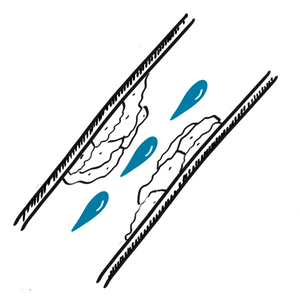

Stenotic artery caused by plaque